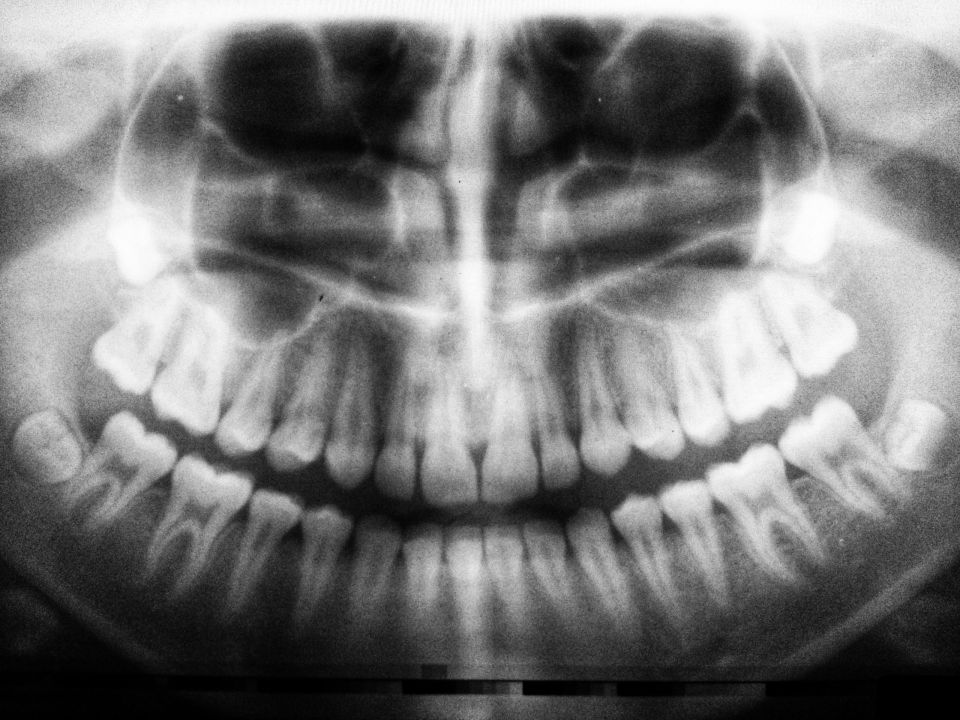

Zahnärztliche Chirurgie

In unserer fachärztlichen Praxis für Mund-, Kiefer- und Gesichtschirurgie sind wir in besonderer Weise auf die orale Chirurgie spezialisiert. Der Einsatz modernster Technik und eine besondere Sorgfalt sind hierbei die Voraussetzungen für eine sichere chirurgische Behandlung. Für uns sind ein schonendes Vorgehen und eine für sie angenehme, schmerzfreie Behandlung besonders wichtig.

Unseren hohen fachärztlichen Standard runden wir regelmäßig durch Fortbildungen ab, um im Bereich der oralen Chirurgie stets auf dem neuesten Stand zu sein. Neben Implantationen und Knochenaufbau bieten wir unseren Patienten das gesamte Spektrum der modernen Mund-, Kiefer- und Gesichtschirurgie.

unsere Zahnärztliche Chirurgie im Überblick: